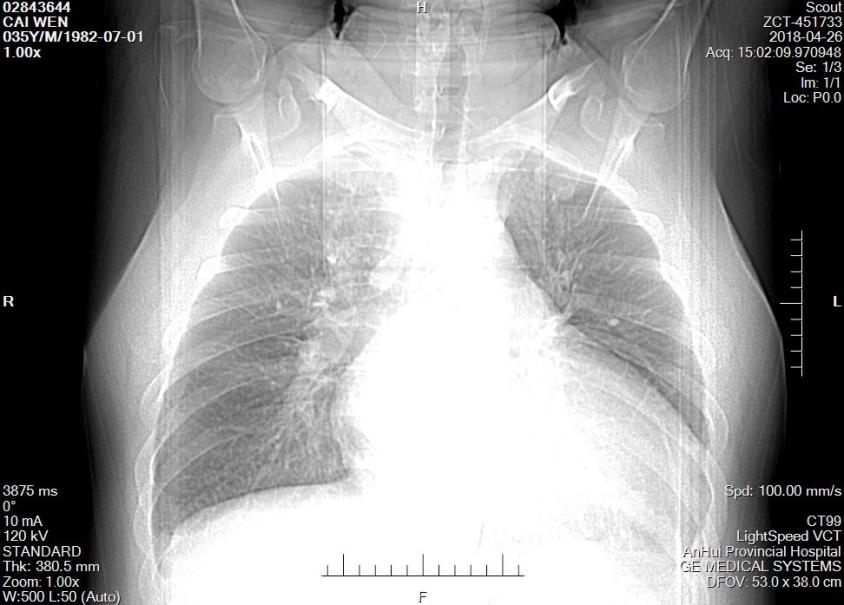

▎ 胸片:心影增大、肺部感染。

图2:患者入院胸片

图5:患者药物治疗前后胸片检查对比